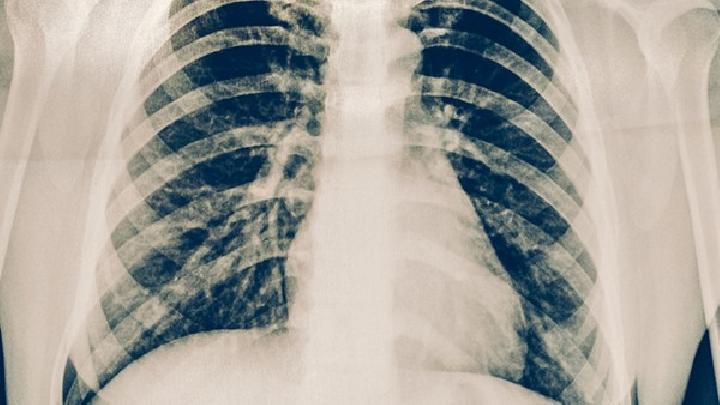

肺癌的基本分类都有哪些 肺癌哪些治疗方法最有效

肺癌已经成为目前世界上发病率最高的一种肿瘤疾病了,越来越多的人都得了肺癌,得了这种疾病可谓是活受罪。既然已经得了这种疾病了,那就放宽心治疗吧!不同类型的肺癌治疗方法是不一样的,接下来我们就一起了解一下肺癌的基本分类以及治疗方法吧!